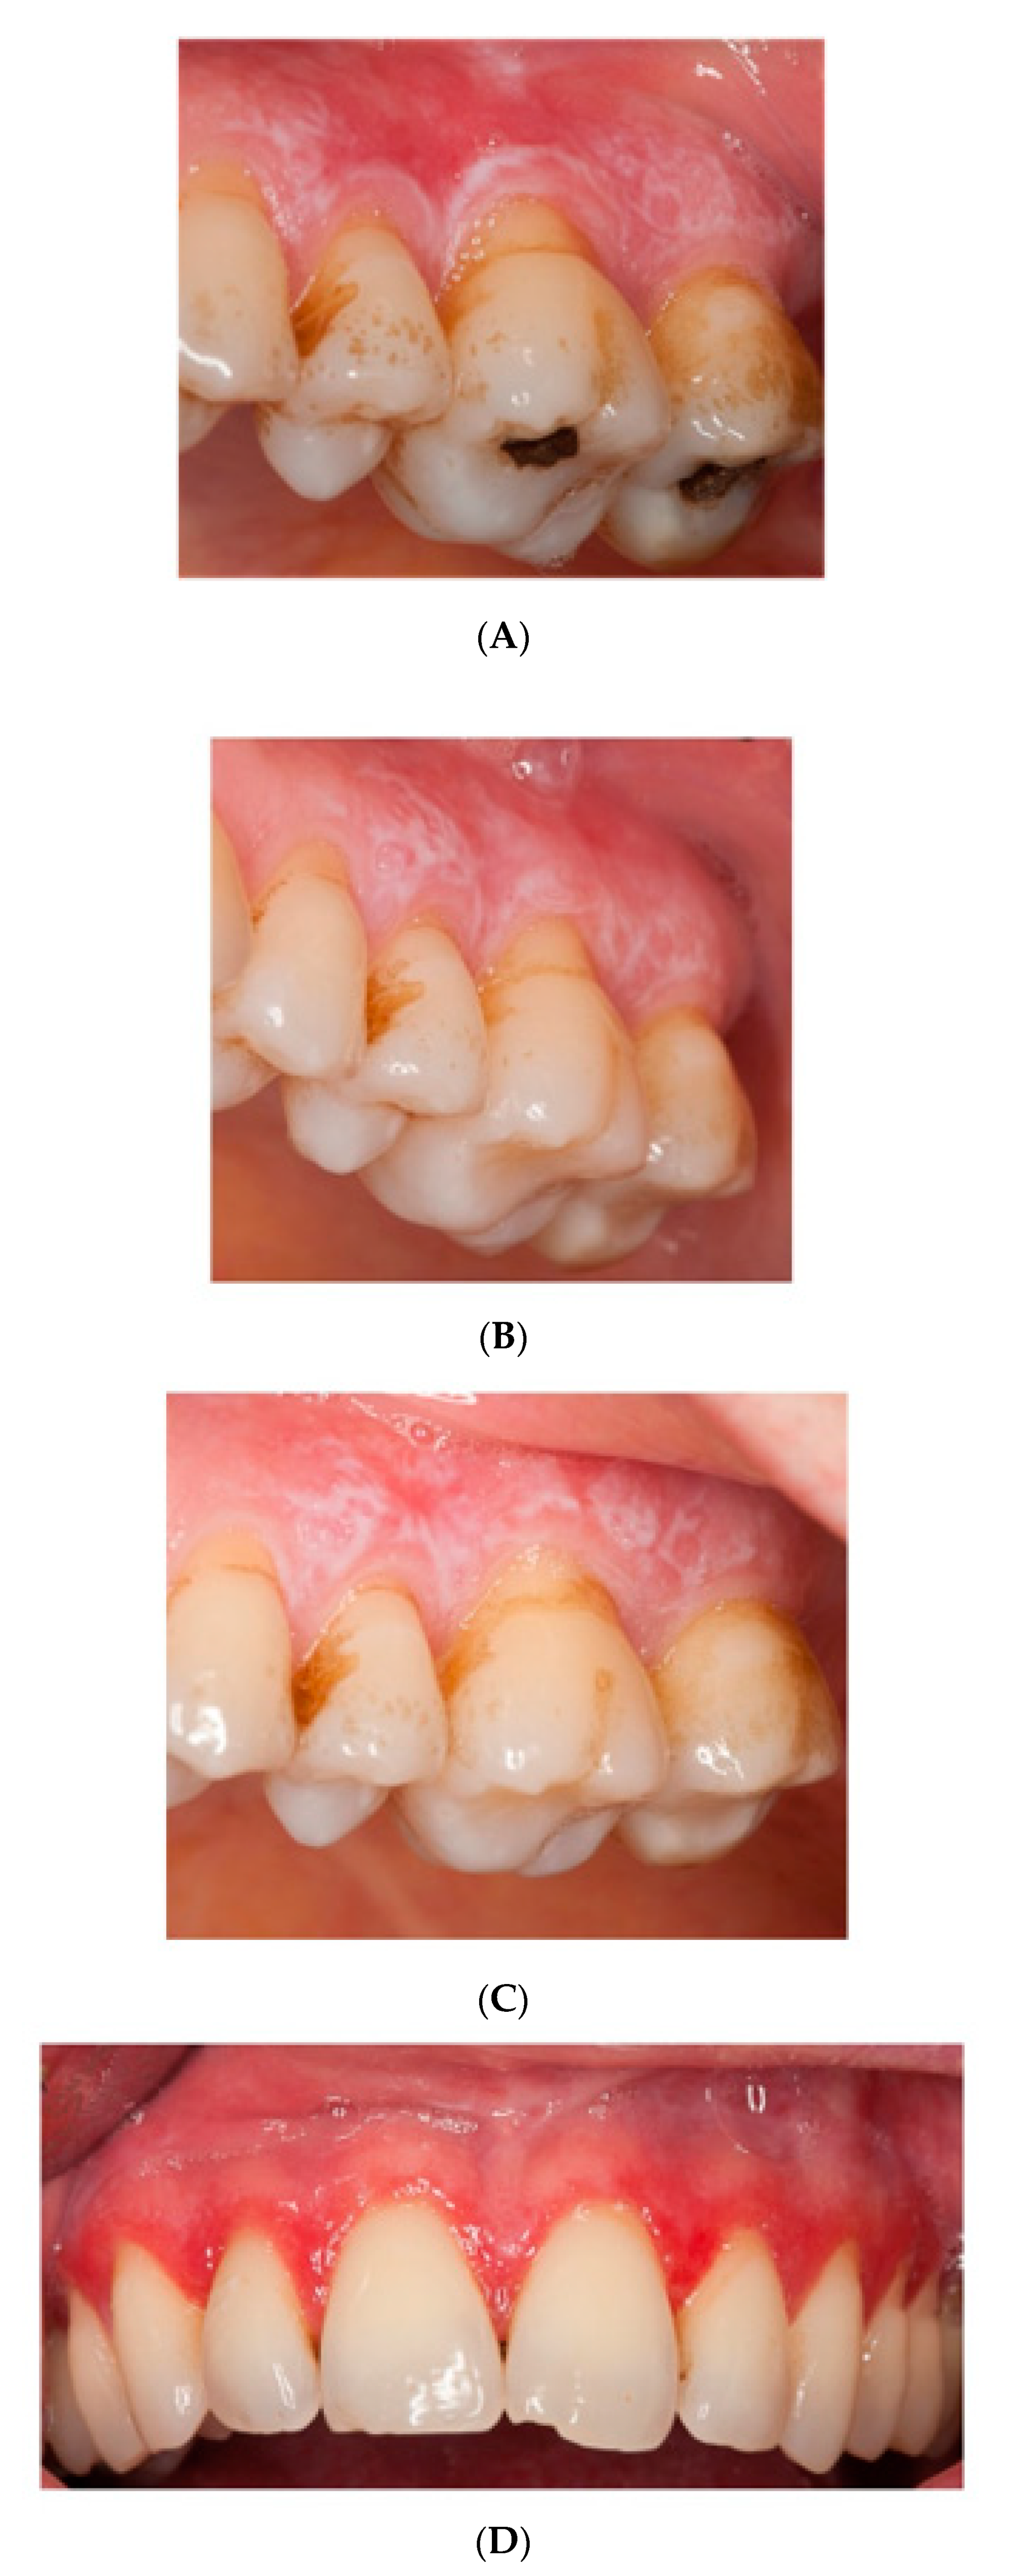

3.5. Clinical Severity Index